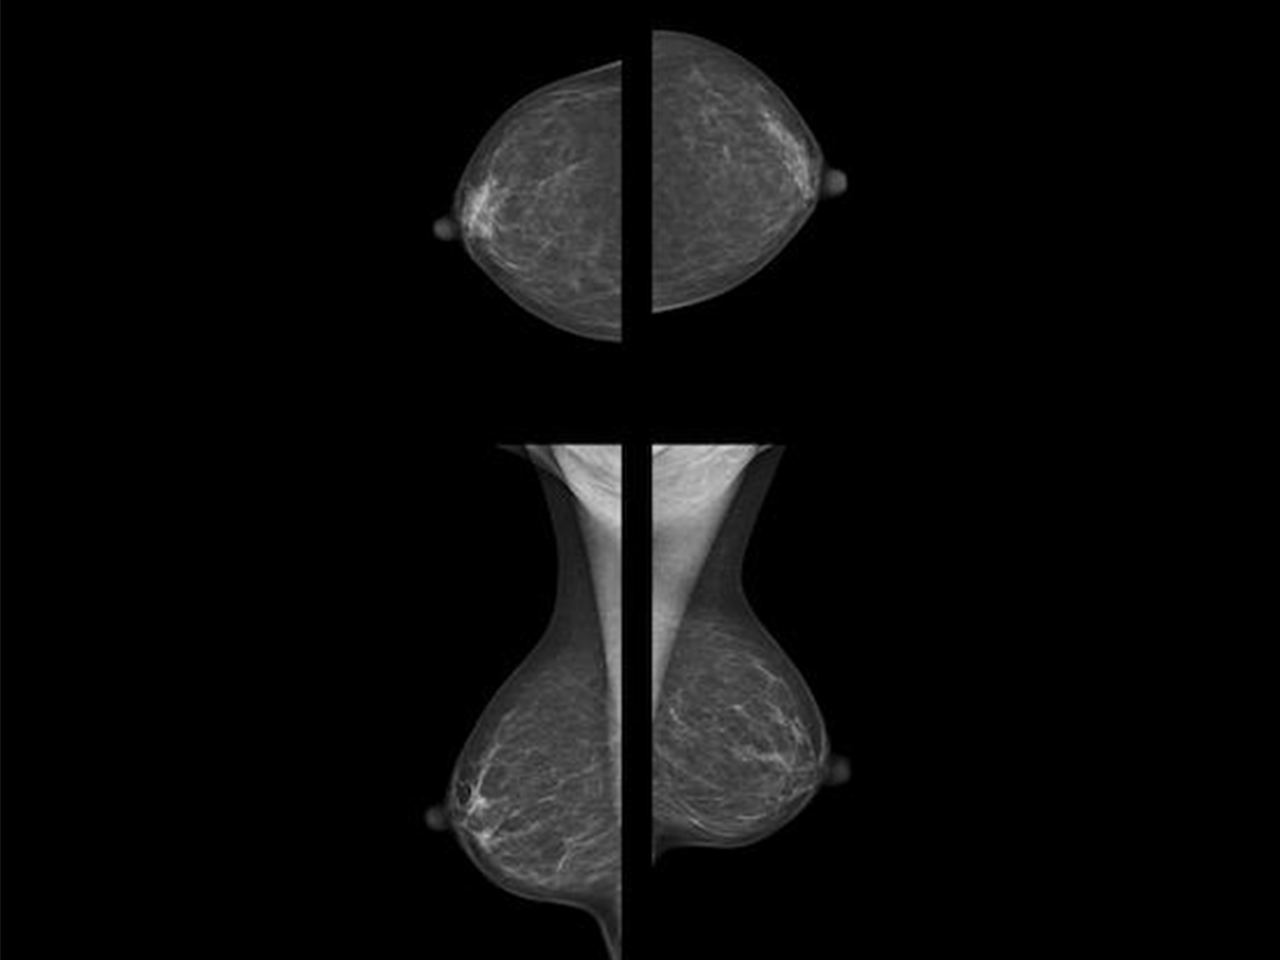

Acte de presentació de la consulta oberta al mercat (o consulta preliminar de mercat, CPM) per recollir la disponibilitat del mercat, o les possibilitats de que el mercat pugui proveir i integrar de manera sistèmica, solucions basades en IA per donar suport al programa de detecció precoç de càncer de mama de Catalunya. En concret, és de principal interès, que l’aplicació d’eines d’IA permeti optimitzar els recursos del programa de detecció precoç, facilitant l’ampliació de la franja d’edat del cribratge (de 45 als 74 anys) garantint la supervisió humana i la qualitat del servei.